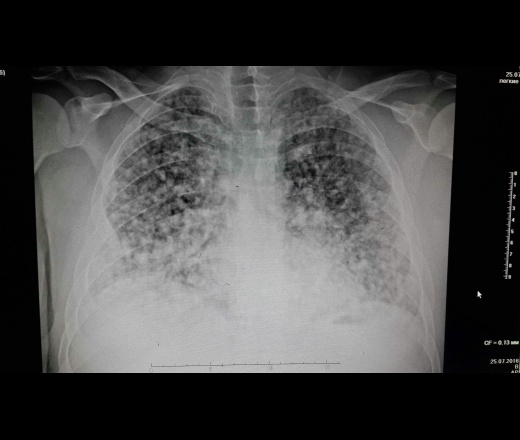

ΠΌΠΎΠΆΠ½ΠΎ ΡΠ²ΠΈΠ΄Π΅ΡΡ Π½Π° ΠΠ’, ΠΠ Π’, ΡΠ΅Π½ΡΠ³Π΅Π½ΠΎΠ³ΡΠ°ΡΠΈΠΈ ΠΈΠ»ΠΈ ΠΠΠ’-ΡΠΊΠ°Π½ΠΈΡΠΎΠ²Π°Π½ΠΈΠΈ. ΠΠΎΠ΄ΡΠ²Π΅ΡΠΆΠ΄Π°Π΅Ρ Π±ΠΎΠ»Π΅Π·Π½Ρ Π±ΡΠΎΠ½Ρ